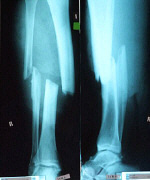

Nekem is izületbe hatoló törés volt, mivel a sípcsont felső része hasadt és elmozdult a helyéről.A törés vége roncsolt amit tudott. A szalagok nem elszakadtak,hanem kiszakadtak a helyükről...(állítólag így jobban jártam, mintha szakadtak volna(?) ) Hazajöttem, itthon műtöttek. Tokától-bokáig begipszeltek a szokásos ideig. Amikor levették a gipszet, úgy jártam mint Renrol. Egyszerűen nem tudtam behajlítani a lábam. Fokról, fokra haladtunk előre. Nagy kínlódás volt. A mai napig nem tökéletes. Neked ezzel nincs gond? A csavarokat, és a támasztólemezt a jövő hónapban veszik ki. Úgy tudom, hogy általában egy évig maradnak benn. Neked is letelt az egy év. Kiveszik?

Egy pár csavar eltéréssel, akár lehetne az én lábam is...

Képek  1 (2).jpg  55 KB  letöltve 2708 alkalommal